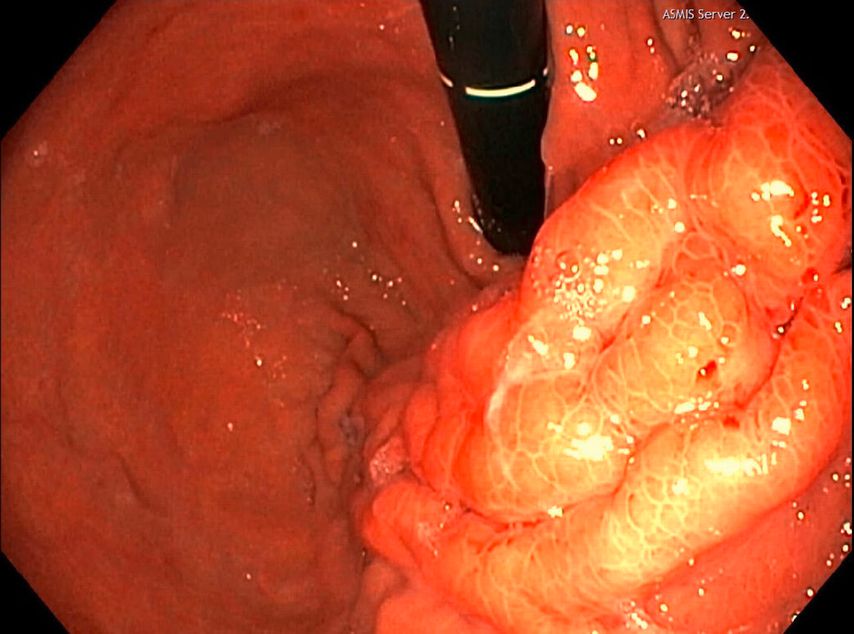

Eine Gastroskopie unter Intubationsnarkose wird angeschlossen (Abb.2). Gastroskopisch ist der Magen leer, die Schleimhaut adäquat durchblutet, ohne Ulzerationen oder malignomsuspekte Areale. Die einzige Auffälligkeit: Der Magen entfaltet sich nicht gänzlich, und zwar aufgrund einer submukös liegenden, verdrängenden Raumforderung im Bereich der Magenvorderwand. Aufgrund der Raumforderung kann der Pylorus nicht eingesehen werden.

Im Rahmen der Narkose wird eine Sonografie des Abdomens ergänzt, in der sich nun der Verdacht bestätigt, dass die große Fluidokollektion nicht im Magen, sondern intramural in der ventralen Magenwand liegt.

Es folgen eine sonografisch gezielte Punktion und perkutane Pigtail-Drainageanlage in die Fluidokollektion (Abb.3). Prompt entleeren sich 2,8l Pus. Die Drainage wird regelmäßig gespült und für 10 Tage belassen. In der Kultur des Punktats können Streptococcus anginosus und Klebsiella pneumoniae nachgewiesen werden, die initial eingeleitete Antibiose mit Piperacillin/Tazobactam wird antibiogrammgerecht umgestellt. Eine Kontrollgastroskopie (Abb.4) zeigt einen unauffälligen Befund am Pylorus und im Bulbus sowie in der Pars descendens duodeni, zahlreiche Biopsien der Magenschleimhaut ergeben eine geringgradige chronische, inaktive Corpusgastritis mit mukosalem Ödem.